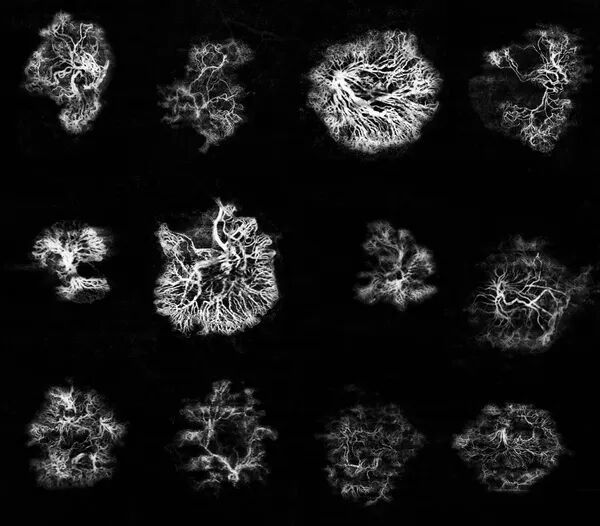

Diabetic Retinopathy Volume on OCTA

Amazing imaging performed by CRT using TowardPi

Performed by Kamal El Madjoubi and Nika Vrabic, CRT.

Branch Vein Occlusion : OCTA Patterns by Toward Pi imaging

Juste pour la beauté des images

Detection of MNV on OCTA using Toward Pi

11 mars 2025

MNV patterns observed on OCTA using Toward Pi device

Even with large PED, MNV were identified in all cases.